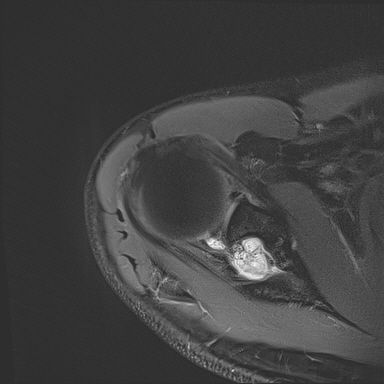

어깨 mri 좀 봐주세요 물혹있다고 하는데 수술해야 하나요?

하도 안 나아서 우측 견관절도 mri 촬영을 했는데 물혹이 있네요